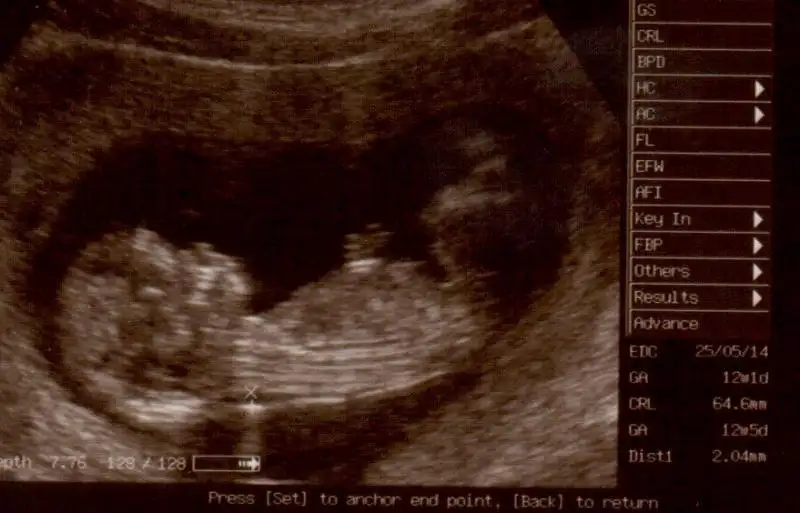

canım bıde buna bakarmısın nolur 12 + 5 Eki Görüntüle 857255 Eki Görüntüle 857256